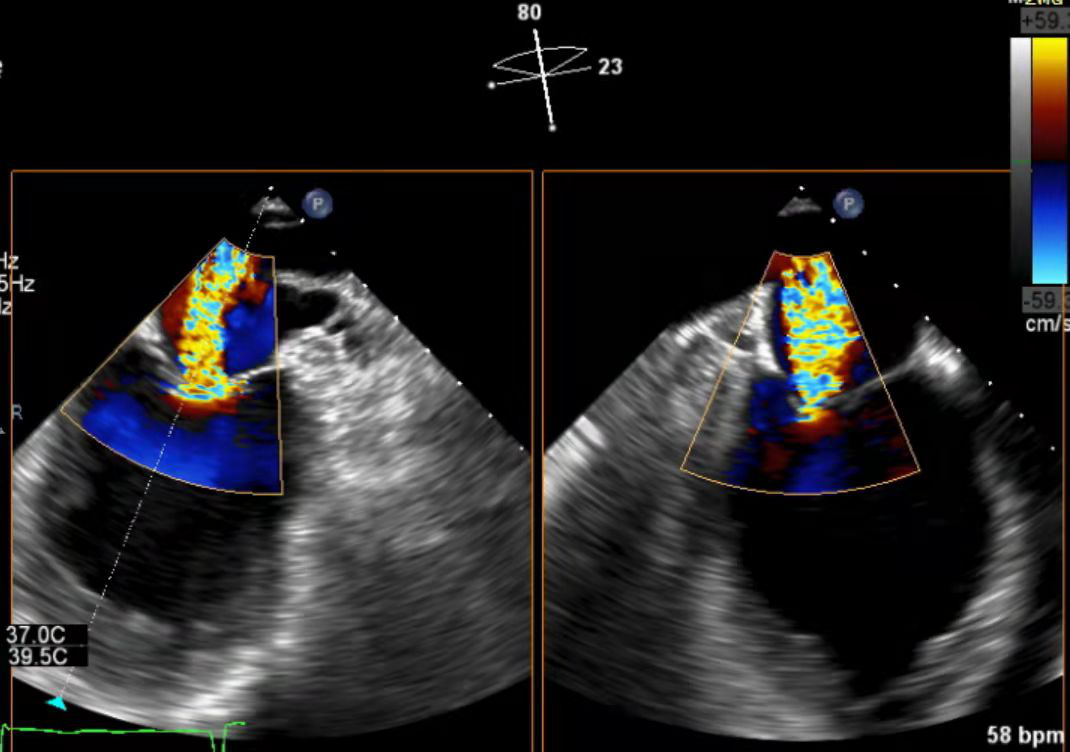

患者为47岁男性患者,受活动后胸闷气短困扰七年余,诊断为扩张型心肌病、心脏扩大、二尖瓣反流(重度),优化药物治疗后仍反复活动后气促,术前经胸超声心电图检查提示二尖瓣中重度反流,左室舒张末径66mm,左室收缩末径56mm,左室射血分数35%,缩流颈宽度0.65cm, 有效反流口面积0.49cm²,二尖瓣瓣口面积4.81cm²,心功能不全表现严重。

手术在患者全麻状态下进行,经股静脉入路,穿刺房间隔后在经食道超声和DSA引导下将瓣膜夹器械输送到左心室,采取单独捕捉策略,先后钳夹二尖瓣前叶和后叶并关闭瓣膜夹,经食道超声反复确认手术效果后,最终释放0609型瓣膜夹,患者术后平均跨瓣压差3mmHg,患者即刻二尖瓣轻度反流,术后第二天自觉临床症状改善明显。

术前心超

术后心超